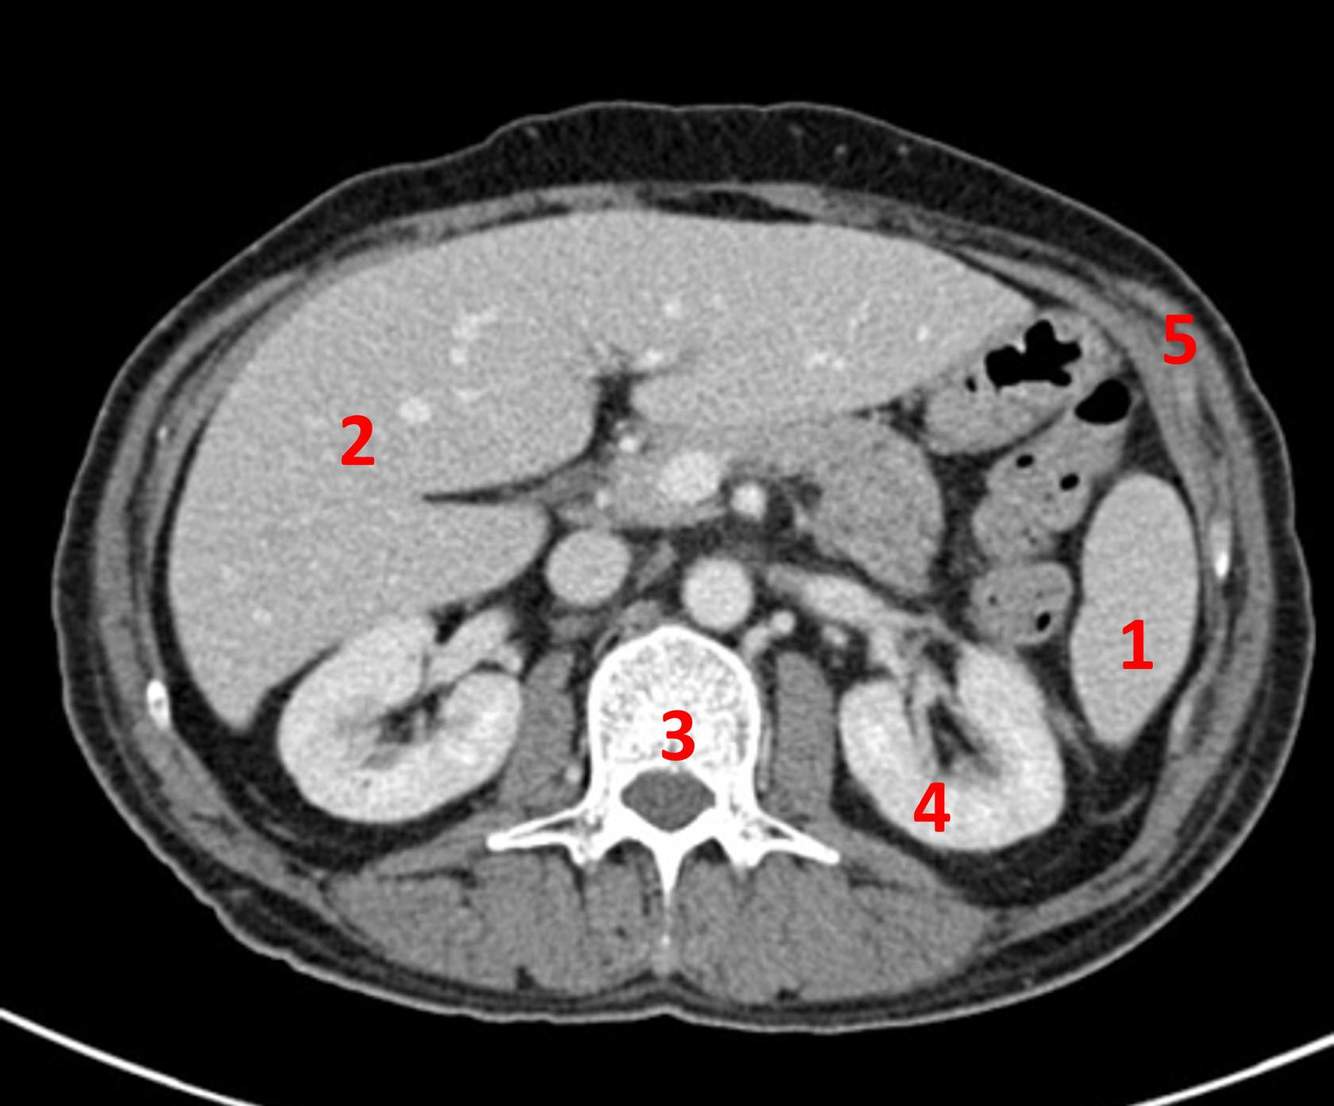

Name the numbered anatomical structures on this abdominal CT.

A

1) Spleen

2) Liver

3) Lumbar vertebra

4) Kidney

5) Abdominal wall